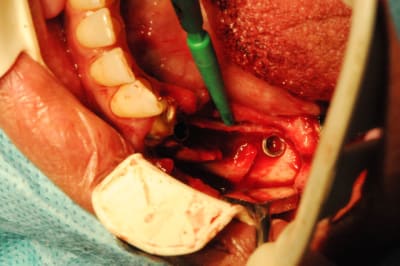

;Les photos:

1:

état initial,

disque diamanté

scie circulaire

2:

Ostéotome "lame" angulé

lame 15 (fréquent dans ce cas )

Ostéotome droit

tous sont manipulés avec douceur, mais aussi impactés avec le maillet chirurgical

3:

de nouveau ostéotome "lame" angulé

Ostéotome droit, plus étroit que le premier.

4:

évolution

Tatum D1

5:

évolution il faut obtenir de quoi placer un diamètre 3,4

de nouveau lame 15 pour incision de décharge verticale

6

lame 15

manuel et impacté au maillet (cool)